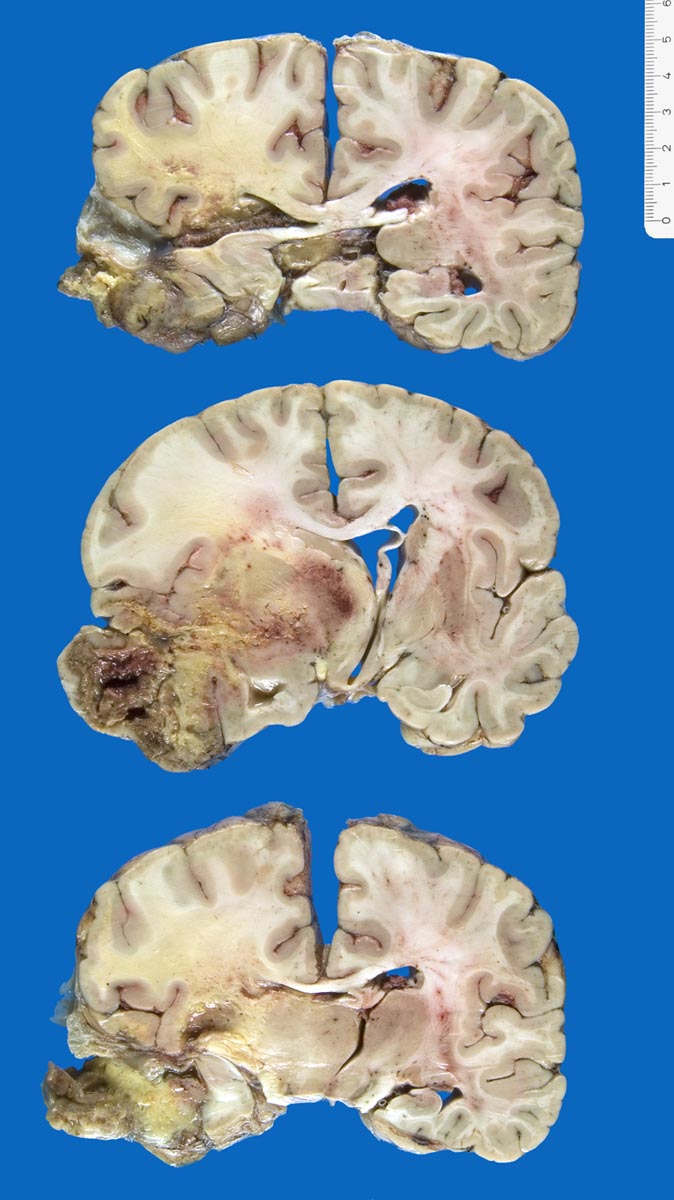

PathoPic – image database / PathoPic ID 9869 - Glioblastoma multiforme

Glioblastoma multiforme

Tumor (Durchmesser 9x8x7cm) links temporal mit zentraler Nekrose und Einblutugen. Mittellinienverschiebung um 1cm und subfalxiale Herniation nach rechts. Einbruch des Tumors in das Ventrikelsystem des Hirns. Einblutung in die Stammganglien.

Histologisch Rest-/Rezidivtumor eines Glioblastoma multiforme (WHO Grad IV) mit ausgeprägten aktinischen Veränderungen.

Glioblastoma multiforme parietal links. WHO Grad IV, Erstdiagnose vor 2 Jahren. Status nach dreimaliger Kraniotomie und Exzision sowie externer und interner Radiotherapie und Chemotherapie. Aspirationspneumonie.